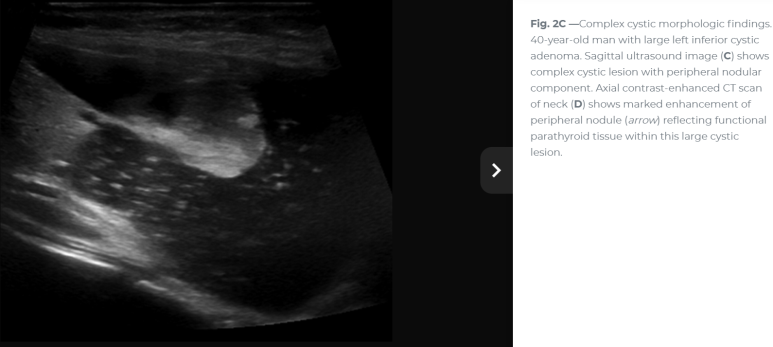

연속 사진으로 내측의 경계가 불규칙하거나 격벽 변화가 있는 모습

확대하면 두꺼운 벽처럼 보이는 부분도 있다. 거꾸로 아래쪽 어두운 곳은 낭성 변화

Imaging included parathyroid ultrasonography, which revealed a cystic appearing mass with septations and mild irregularity (격벽과 불규칙한 내부 경계를 보이는 낭성 종괴)

이번 사례와 같은 위치에 비슷한 모습

For nonfunctional parathyroid cysts, which are usually large simple epithelial cysts, the sonographic features are unlikely to add much specificity to the diagnosis. The primary role of ultrasound in these cases is to guide cyst aspiration for PTH assay to confirm parathyroid origin and potentially for therapeutic intervention. 비기능성 낭종일 경우 초음파의 주된 역할은 부갑상선 기원을 확인하기 위해 PTH assay를 위해 낭종 흡인을 보하는 것이다.

Less common entities to be considered in the differential diagnosis of cystic neck lesions encountered in the typical locations of the parathyroid glands include nodal metastatic lesions that can typically appear cystic, 낭종처럼 보일 수 있는 림프절 전이성 병변 (e.g., lymphoma, squamous cell carcinoma, papillary thyroid cancer - 림프종, 편평세포암종, 갑상선유두암등..) and cervical thymic cysts 흉선 낭종. The typical locations of other cystic neck masses, such as second branchial cleft cysts (anterior to the sternocleidomastoid muscle near the angle of the mandible) and thyroglossal duct cysts (suprathyroidal midline lesion embedded in strap muscles), can suggest the diagnosis, but prospective definitive differentiation of these rare lesions on the basis of sonographic appearance and location alone may not be possible 그러나 초음파 모습만으로 흔하지 않은 병변과의 확정적 감별은 가능하지 않다. When parathyroid origin is suspected, cyst aspiration for PTH assay is a safe and specific method of confirmation. 부갑상선 기원이 의심되면 흡인을 하여 PTH assay를 하는 것이 확인을 위해 안전하고 특이적인 방법이 되겠다.